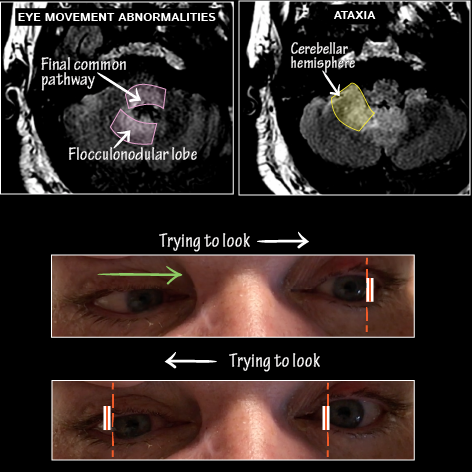

Patient presents with diplopia, vertigo, and incoordination. Exam reveals profound horizontal eye movement abnormalities and right side ataxia.

• MRI imaging demonstrates significant pontine inflammation and right cerebellar inflammation.